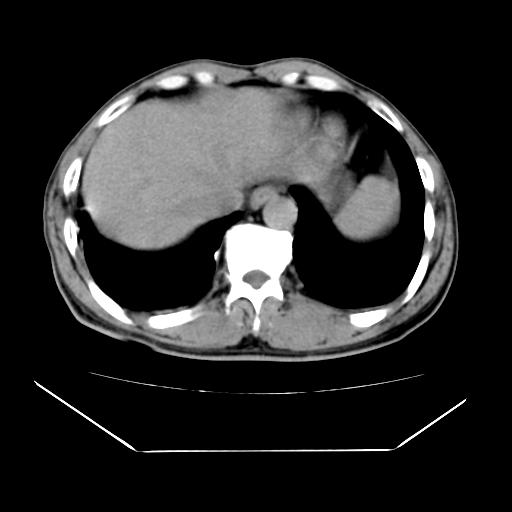

男性,55岁,外院体检afp明显升高,但b超未发现异常,否认乙肝病史。来我院ct增强。有延时扫描。

延时扫描完全充填,血管瘤

肝脏右叶动脉期可见低密度影,至延迟期被充填,考虑血管瘤可能性大。

不排除肝右叶肝癌可能。

如果这个是癌灶的话则下腔静脉有瘤栓可能

肝6段血管瘤

血管瘤可能性大。

考虑肝右静脉影。